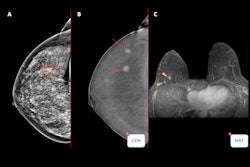

Images depict a 55-year-old woman with a family history of breast cancer who underwent combined mammography and MRI screening. (A) Right and (B) left mediolateral oblique and (C) right and (D) left craniocaudal mammograms show a large known cyst in the left breast (arrow in B and D), but were otherwise assessed as being unremarkable. Breast tissue was judged to be extremely dense. (E) Concurrent axial subtraction MRI scan shows a large, diffuse, invasive lobular cancer (circle) in the right breast. The AI system provided a case-based cancer suspicion score of 8 on a scale of 0-10, which would have led to selection for MRI screening using both the score 5 and score 8 thresholds, but not the score 9 threshold.RSNA